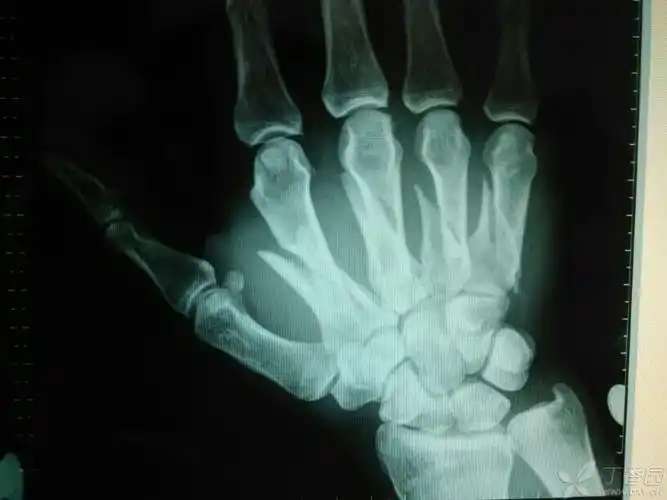

多发掌骨骨折例 [病例帖]